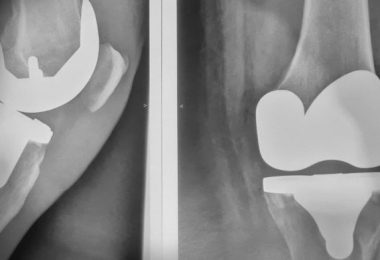

Artrosis, prótesis y recuperación de rodilla

Una rodilla nueva Nota: Este es el artículo de un paciente…